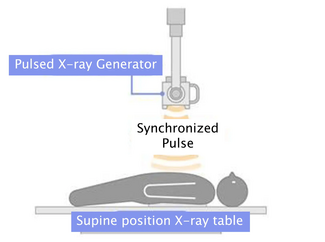

Case Report. A 70-year-old male with a complex past medical history, including  transient ischemic attacks, sick sinus syndrome with pacemaker placement, bilateral renal transplants secondary to glomerulonephritis and bovine aortic valve replacement, initially presented with acute onset of facial swelling. Imaging from an outside facility demonstrated superior vena cava compression from the left subclavian vein, which was thought to be related to occlusive thrombus on his pacemaker wires. He was placed on anticoagulation, instructed to sleep at a

transient ischemic attacks, sick sinus syndrome with pacemaker placement, bilateral renal transplants secondary to glomerulonephritis and bovine aortic valve replacement, initially presented with acute onset of facial swelling. Imaging from an outside facility demonstrated superior vena cava compression from the left subclavian vein, which was thought to be related to occlusive thrombus on his pacemaker wires. He was placed on anticoagulation, instructed to sleep at a  45° angle and brought to the catheterization lab, where balloon angioplasty of the left subclavian and innominate veins was performed, despite not finding a significant stenosis in this area. It was thought that the anticoagulation had resulted in resolution of clot burden prior to the procedure. The patient was seen in follow-up two weeks later with return of his facial swelling while sleeping flat. This usually resolved during the course of the day with normal activities. He was continued on anticoagulation and followed clinically. He presented one month later with sweats, abdominal pain and flu-like symptoms. Further imaging revealed a large right atrial mass with hypermetabolic activity on positron emission tomography scan (Figures 1A, 1B and 2). The patient was referred to cardiac catheterization for a tissue diagnosis.

45° angle and brought to the catheterization lab, where balloon angioplasty of the left subclavian and innominate veins was performed, despite not finding a significant stenosis in this area. It was thought that the anticoagulation had resulted in resolution of clot burden prior to the procedure. The patient was seen in follow-up two weeks later with return of his facial swelling while sleeping flat. This usually resolved during the course of the day with normal activities. He was continued on anticoagulation and followed clinically. He presented one month later with sweats, abdominal pain and flu-like symptoms. Further imaging revealed a large right atrial mass with hypermetabolic activity on positron emission tomography scan (Figures 1A, 1B and 2). The patient was referred to cardiac catheterization for a tissue diagnosis.

Two 8 French (Fr) sheaths (Cordis Corporation, Warren, New Jersey) were  placed in the right femoral vein. A right atrial angiogram was performed with a 6 Fr pigtail catheter (Cordis Corporation) (Figure 3). An 8 Fr Acuson AcuNav intracardiac echo probe (Siemens Medical USA, Malvern, Pennsylvania) was inserted into the right atrium. This was used to visualize the mass (Figure 4). A Mullins sheath (Medtronic, Inc., Minneapolis, Minnesota) was used to guide biopsy forceps (Argon Medical, Athens, Texas) to obtain specimens from the right atrial mass (Figure 5).

placed in the right femoral vein. A right atrial angiogram was performed with a 6 Fr pigtail catheter (Cordis Corporation) (Figure 3). An 8 Fr Acuson AcuNav intracardiac echo probe (Siemens Medical USA, Malvern, Pennsylvania) was inserted into the right atrium. This was used to visualize the mass (Figure 4). A Mullins sheath (Medtronic, Inc., Minneapolis, Minnesota) was used to guide biopsy forceps (Argon Medical, Athens, Texas) to obtain specimens from the right atrial mass (Figure 5).